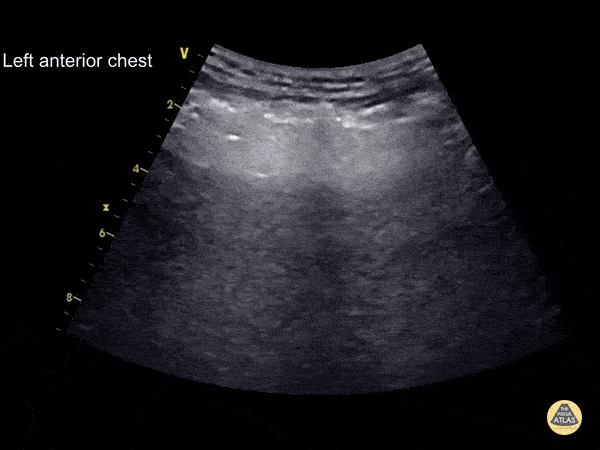

This patient fell 5m onto a slab of concrete. The curvilinear transducer was used for the EFAST survey of his left anterior chest wall Hyperechoic irregular lines are seen superficial to the ribs (E lines - subcutaneous emphysema). These arise from air trapped in the soft tissue under the skin and should not be mistaken for the pleural line. Subcutaneous emphysema obscures the rib shadow and pleural line that lie below it Learning point : the pleural line lies underneath the level of the ribs, subcutaneous emphysema lies above the level of the ribs This patient had a large left-sided pneumothorax and an intercostal drain was placed followed by a serratus anterior plane block for analgesia Dr. Cian McDermott - Dublin, Ireland